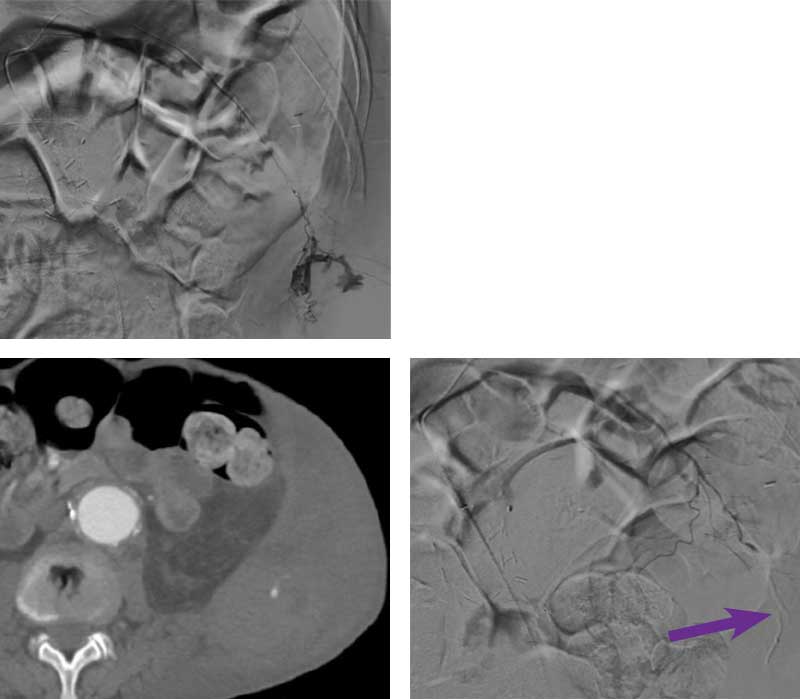

67-year-old male with a history of a 4.7 cm abdominal aortic aneurysm, remote history rectal cancer status post resection, heart failure with reduced ejection fraction and CAD presents to the ED with disabling acute onset left hip pain and an expanding left flank mass. The patient is on dual anti-platelet therapy for percutaneous coronary intervention within the past year. The patient denied any history of falls or trauma. On presentation the patient was hemodynamically stable.

Intervention used

A 5 Fr x 40 cm Destination™ Sheath was placed in the right common femoral artery. An aortogram was performed with a 5 Fr pigtail catheter from the suprarenal abdominal aorta, which demonstrated active extravasation from the left L1 lumbar artery. A 5 Fr Headhunter catheter was used to select the left L1 lumbar artery, and distal navigation was achieved with a microcatheter and Fathom™ 16 Steerable Guidewire. The distal L1 lumbar artery was embolized with 0.3 mL of Obsidio Embolic using the standard technique. Completion angiography from the proximal left L1 lumbar artery demonstrated a static contrast column with no evidence of extravasation.

Scan images from Obsidio lumbar artery embolization case.